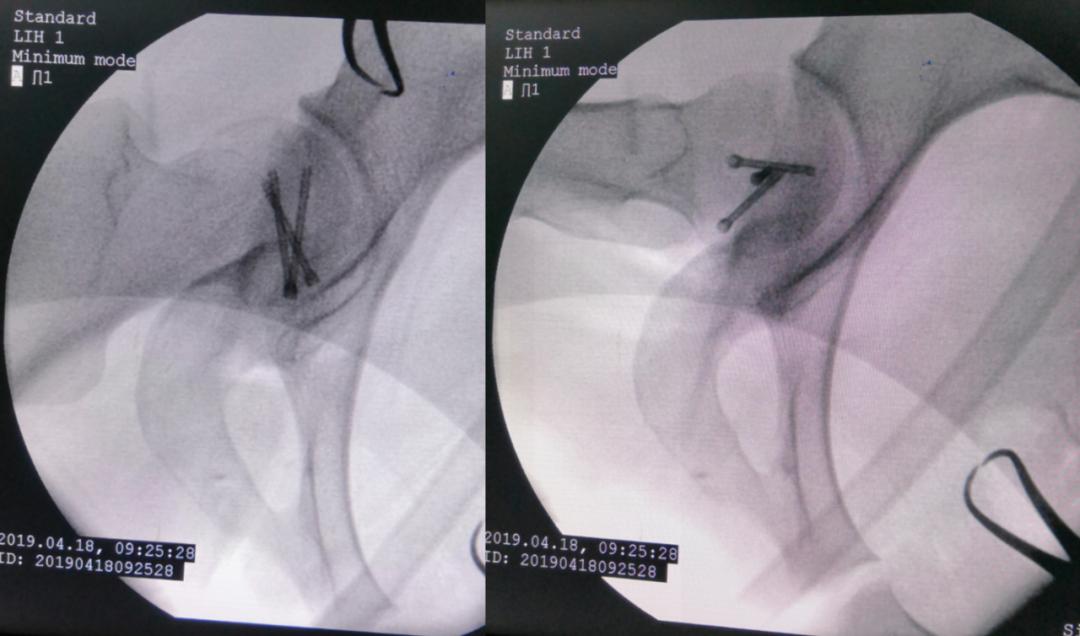

术中资料

对横跨切口远端的旋股内侧动脉血管束应特别注意,其自股骨颈的前方经内侧绕至后方延伸为旋股内侧动脉深支,是股骨头血供的主要来源。